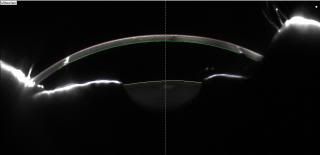

Below are the Pentacam scans of my grafts taken in 2011, right graft then was 22 years and the left was just getting ready to celebrate its 21st birthday. When these were taken I had already been seeing through someone elses corneas for longer than I had seen out of my own and both grafts are still going strong!

You can see that it appeasr i am looking up but that is just the orientation of the picture, but you can clearly see a white vertical line which is the scar tissue where the graft joins to the old cornea. "New" cornea is highlighted with a red line on top and a green line below as this was used by the consultant to get an idea of how thick the graft is. The horizontal line is the iris and the smudge like a bowl with the yellow line on top is the lens of the eye.

LEFT

RIGHT